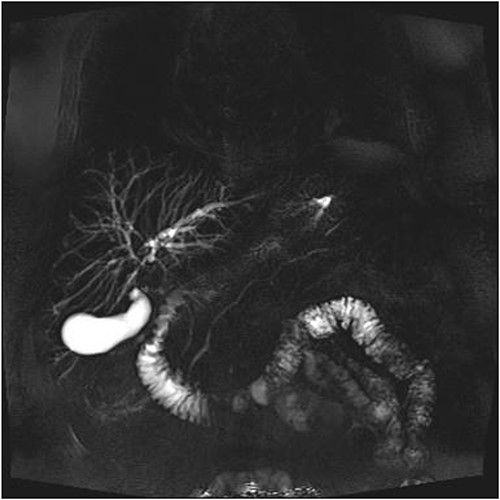

A man in his 70s presented to the emergency department with painless obstructive jaundice with dark urine and pale stools. The patient denied having any fever, nausea, vomiting, or weight loss. Liver function test progressively worsened during the admission peaking at a bilirubin of 287 umol/L (normal 2–20), alkaline phosphatase 694 U/L (normal 30–110), and alanine aminotransferase 160 U/L (normal < 40). Initial assessment on computed tomography and ultrasound raised concerns for primary pancreatic head neoplasm or cholangiocarcinoma (Fig. 1). He subsequently underwent magnetic resonance cholangiopancreatography (MRCP), which showed involvement of the entire common bile duct with no definite stricture or dilatation and no discrete pancreatic head mass (Fig. 2). Positron emission tomography showed abnormal uptake in the intrahepatic and extrahepatic bile ducts, focal uptake in the tail of the pancreas, and lymph nodes in the porta hepatis, retroperitoneum, and right iliac fossa (Fig. 3). Tumour markers revealed a carbohydrate antigen 19-9 (CA19-9) of 3286 kU/L (normal < 34).

Repeat liver function test 1 month later showed dramatic improvement, with bilirubin level at 25 umol/L (normal 2–20), total IgG 13.23 g/L (normal 6.5–15.2), IgG4 1.45 g/L (normal 0.04–0.86), and CA19-9 44 (normal < 34). The steroids were gradually tapered and ceased. Repeat MRI 4 months later showed a normal biliary system with complete resolution of the common bile duct pathology (Fig. 4).